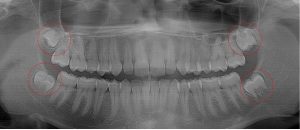

This 19 year old patient has all four 3rd molars present (circled). The roots are +90% formed. Both lower 3rd molars are impacted against the 2nd molars with no chance of further eruption and a +60% probability of decaying before age 30. The patient presented with pain and infection around both lower 3rd molars, requiring immediate extraction